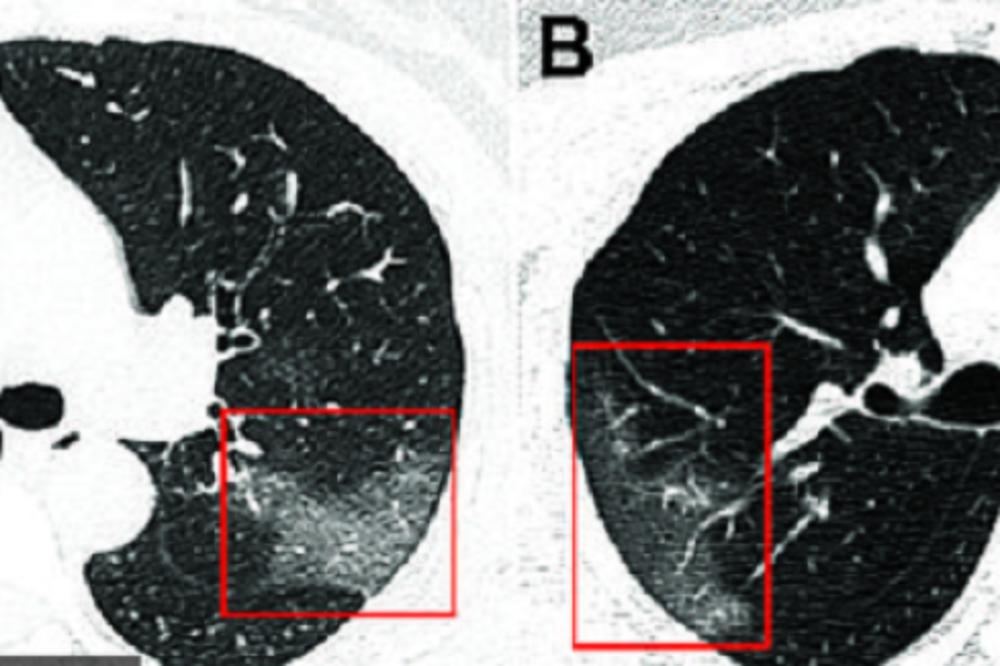

Kod većine je utvrđen sezonski grip, neki su zadržani na lečenju u Infektivnoj klinici, jer su imali ozbiljne gripozne upale pluća.